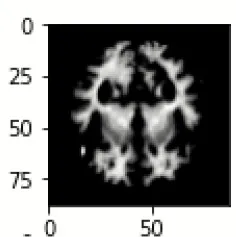

The database used in this study consists of a total of 6,200 AD images that are retrieved from the Kaggle database. It comprises grayscale images of 896 MD, 64 Mod D, 3,200 ND, and 1,966 VMD images, with a dimension of (208 × 176 × 3) pixels. The dataset for evaluation is divided in such a way that 80% of the image samples are utilized for training the model and the remaining 20% are utilized for testing the model (Filipovych et al., 2011). Figure 2 shows the database of MRI images. Table 2 shows the publicly available AD dataset.

FIGURE 2

www.frontiersin.org

Figure 2. Alzheimer's disease: (A) M.D, (B) Mod.D, (C) N.D, and (D) V.M.D.